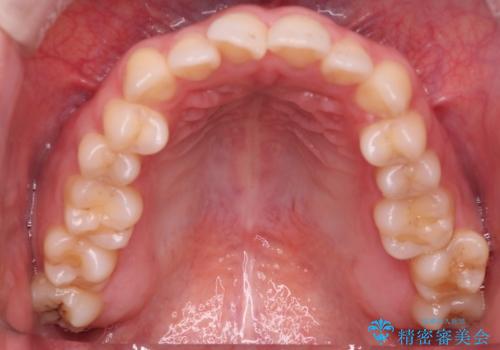

- 前歯の凸凹を主訴に来院された患者様です

骨格性の下顎前突傾向もあったため、臼歯関係の遠心移動も行うことで綺麗な仕上がりで矯正を終了することができました。

遠心移動を行うことで期間はかかりましたが、良い状態で仕上がっています。